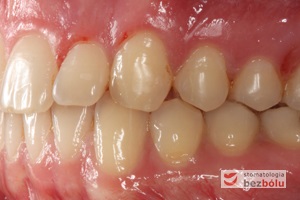

Młody 28-letni, pogodny, stale uśmiechnięty pacjent zgłosił się celem korekcji wad zębowych ograniczających pełną ekspresję uśmiechu. Głównym problemem był dodatkowy siekacz boczny (dwójka) po stronie prawej w łuku górnym. Dodatkowy ząb spowodował stłoczenia pozostałych zębów w łuku górnym oraz przesunięcie linii pośrodkowej. Obliczenia dostępnego miejsca dla siekacza bocznego wpłynęły na wybór zęba przeznaczonego do ekstrakcji. Usunięto dwójkę ustawioną dowargowo, zaś jej „siostrę bliźniaczkę” skierowaną w stronę podniebienia wprowadzono do łuku zębowego w drodze leczenia ortodontycznego. Problemem było szczelne zamknięcie szpary poekstrakcyjnej z powodu nadmiaru miejsca w kości. Wyrównano linię pośrodkową. Leczenie przeprowadzono jednym łukiem ortodontycznym górnym, dolny łuk zębowy nie wymagał założenia aparatu. Po zdjęciu zamków korekcję detali przeprowadzono z użyciem pozycjonera wykonanego w technice termoformingu. Stabilizację efektów leczenia zapewnił stały retainer klejony do powierzchni podniebiennych siekaczy górnych.